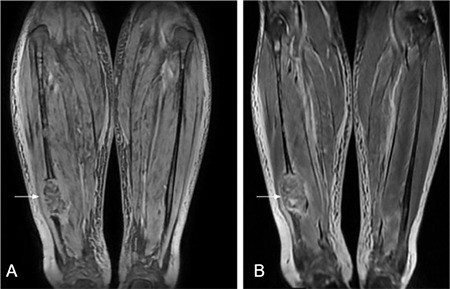

The Curious Tale of a Missing Bone Segment

Abstract Image